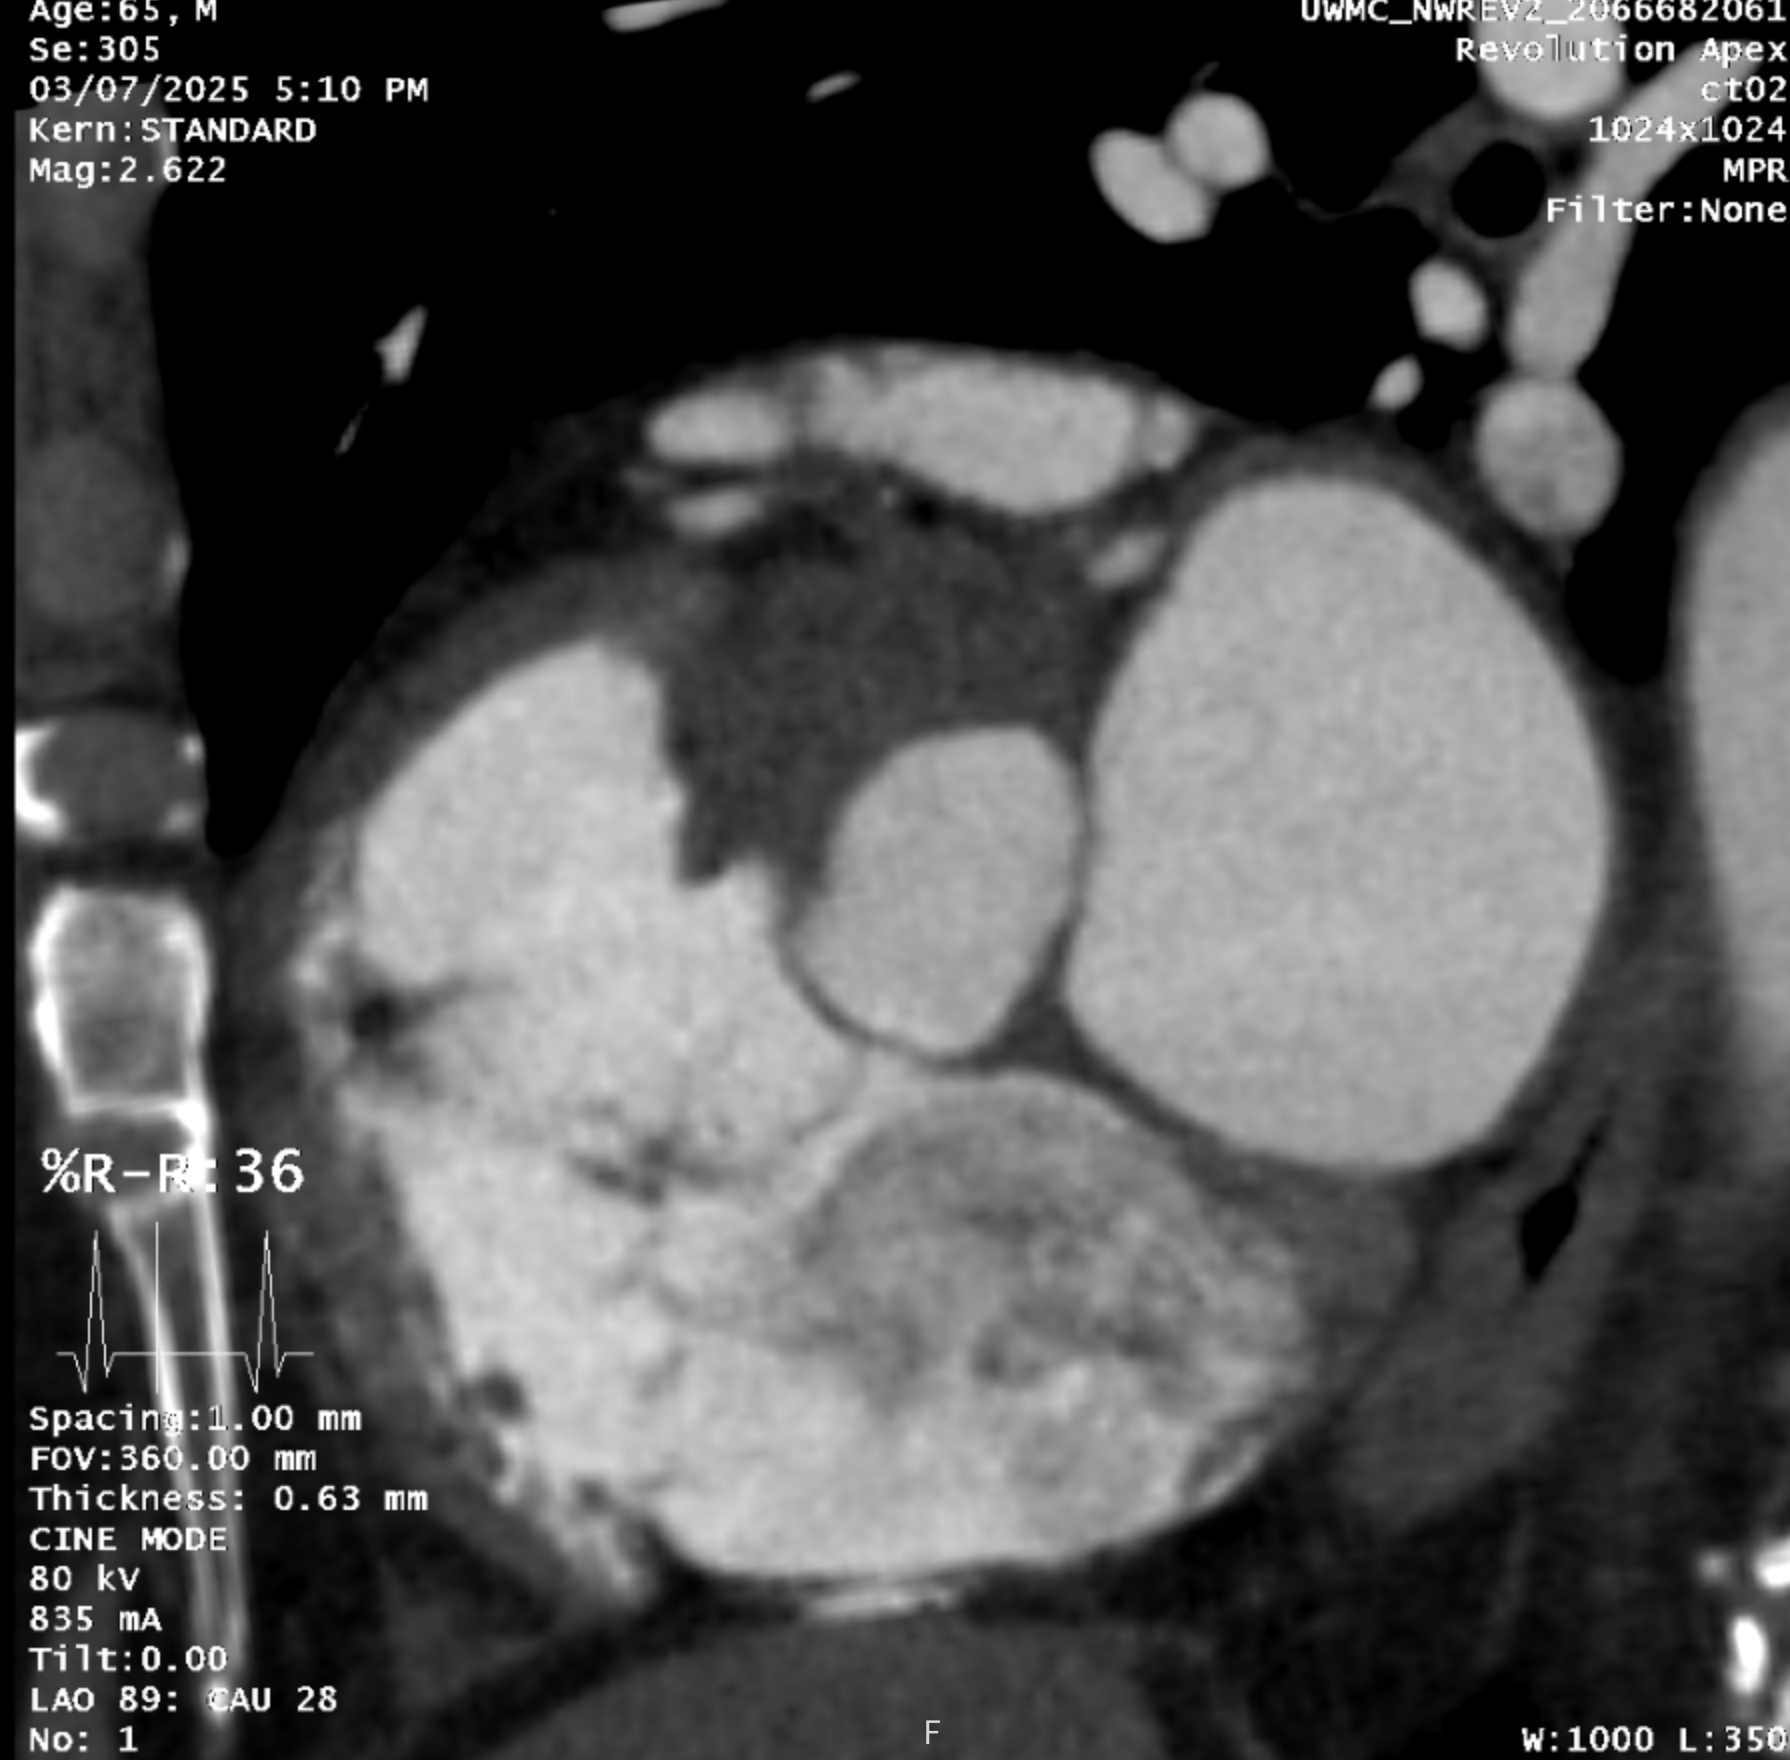

In March, I was diagnosed with severe aortic stenosis after spending most of a weekend in Seattle Northwest Hospital undergoing a battery of tests. The cardiac team zeroed in on my calcified heart valve within hours of admission to the ER. They detected a telltale murmur that’s a possible sign of restrictions in blood flow from the valve’s “leaflets” into the aorta which is how blood cycles back into your body. So yah, I have sticky valve flaps (shown below).

Two CT scans, an electrocardiogram, and an echocardiogram confirmed the severity of the calcification and prompted a rapid succession of consults with the cardiology specialists about surgery. The options are starkly different: thread a new valve up through my arteries to place it next to the faulty one or crack open my chest and replace the bad boy with a bioprosthetic (tissue) valve.